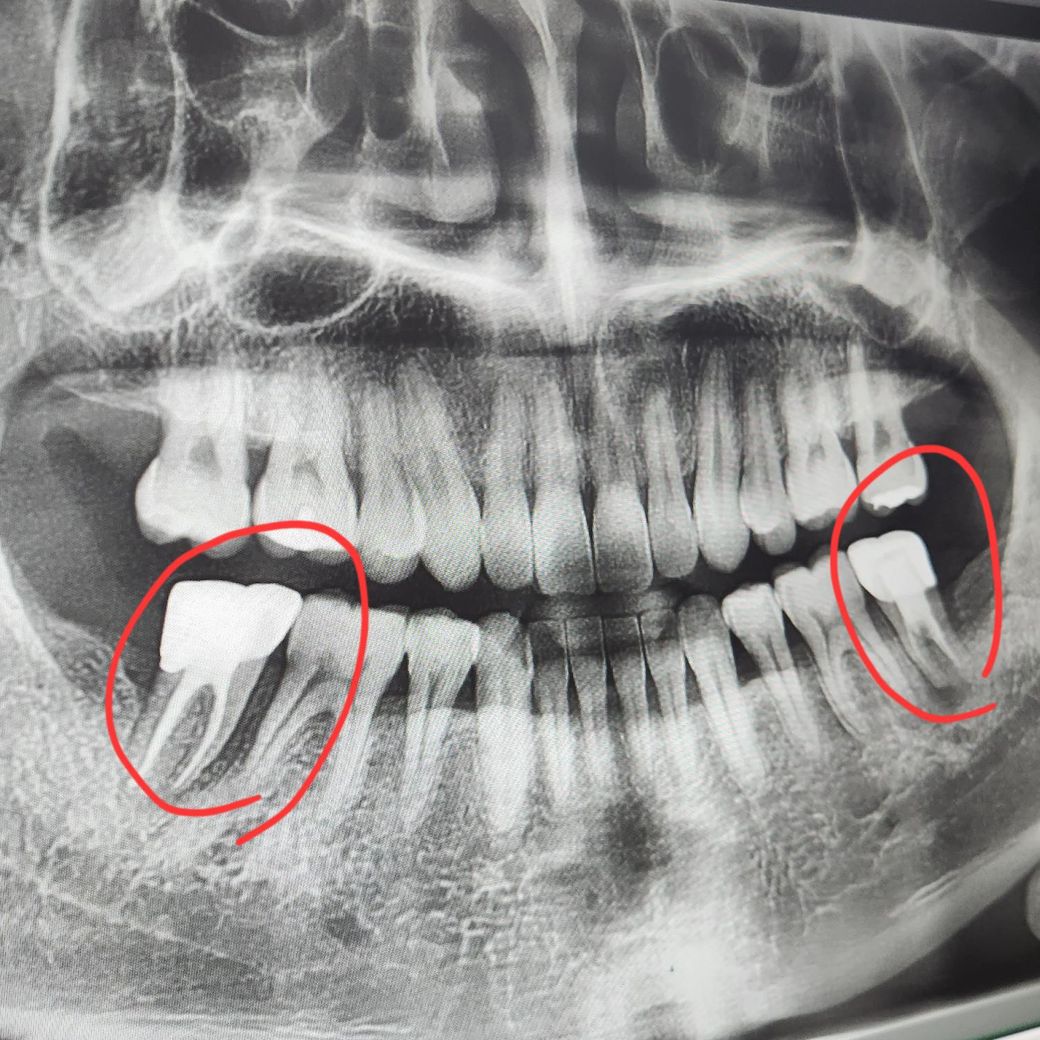

신경치료했던 어금니... 재신경치료 가능할까요?

신경치료하고 크라운 씌운 어금니 두 개인데

최근에 왼쪽 어금니 쪽에 고름이 살짝 잡혀서

엑스레이 찍어보니 염증이 관찰되었다네요

사진으로 봤을 경우에는 치아 주변에 생긴 염증이 커 보입니다. 오른쪽 아래에는 띠처럼 생기는 병소는 치아의 금이 같이 생겼을 수 있으며 왼쪽 아래의 경우에는 치아뿌리 쪽에 상대적으로 큰 염증이 보입니다. 제 신경치료를 시도해볼 순 있지만 이전의 증상이 완전히 없어지지 않을 수 있습니다.

사진상으로 보면 재신경치료 시기는 지난거 같고 둘다 발치를 해야될정도로 치아 상태가 좋지 않은거 같습니다.

지금 엑스레이상 이전 신경치료는 흠잡을데 없을 정도로 잘 되어 있습니다 재신경치료 한다고 지금보다 잘 될 것 같지는 않습니다. 또한 치아 자체뿐만 아니라 치주(잇몸) 상태도 좋지 않습니다.

대학병원 보존과 가셔서 치근단 절제술도 상담받아보실 수 있으나 치아 살릴 확률은 낮습니다.